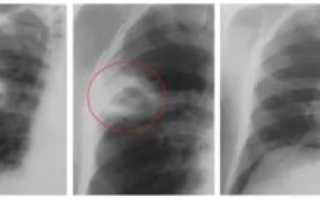

Выполнив рентгеновский снимок в различных проекциях, выявить на нём наличие абсцесса легких можно по присутствию таких факторов:

- выделение признаков, характерных для наличия круглой тени;

- присутствуют нечёткие границы (может свидетельствовать о том, что заболевание сопровождается воспалительным процессом);

- интенсивность средней степени;

- выделяется однородность содержимого (указывает на наличие гнойника);

- рядом с пораженной стороной наблюдается увеличение размеров лимфатических узлов в корне;

- имеется полость распада, которая размещена в средней области просветления;

- утолщенные стенки, при этом внутри они не являются равномерными;

- повышенный или пониженный уровень жидкости во внутренней зоне кольца.

Рентгенограмма абсцесса лёгкого на различных стадиях развития болезни может показать абсолютно разные картины.

На ранних стадиях развития болезни на снимке присутствуют следующие проявления:

- Во время первичных стадий абсцесса пораженная зона небольшая, от 1 до 4 см.

- Вокруг кольцевидной тени размещены очаги воспаления перифокального типа.

- Происходит деформирование легочного рисунка.

- Присутствует тенденция к возрастанию уровня жидкости.

По истечении некоторого времени внутренняя часть стенки кольцевидной тени подвергается уплотнению, и в результате этого исчезают её шероховатости.

Когда абсцесс находится в процессе прорыва гнойника в области бронхов, на снимке с рентгена можно увидеть следующие изменения:

- стенки полости становятся гораздо тоньше;

- в центре пораженной зоны присутствует просветление, где имеется горизонтальный уровень жидкости;

- выше имеющегося уровня жидкости присутствуют области с некрозом тканей;

- по причине воспаления по гнойному типу внешняя сторона капсулы становится не такой четкой.

А вот для определения очистившейся формы легочного абсцесса следует обратить внимание на следующие моменты:

- стенки капсулы становятся намного тоньше;

- отсутствует уровень жидкости;

- происходит зарастание стенок полости с помощью соединительной ткани, это способствует тому, что очистившийся абсцесс ещё какое-то время остаётся в первичном размере, а затем заменяется рубцом.

Рентгенологические признаки в стадии распада (прорыва абсцесса в бронхи) отличаются более выраженной картиной, позволяющей определить полость с уровнем жидкости, увидеть газ, расположенный над жидкостью в виде осветленного полукруга.

Для выявления размеров и расположения полостей снимки рекомендуется делать в нескольких стадиях наполнения плевральной полости жидкостью, например, до и после отхаркивания и в нескольких проекциях. Полость абсцесса на рентгенологических снимках чаще всего имеет овальную форму.